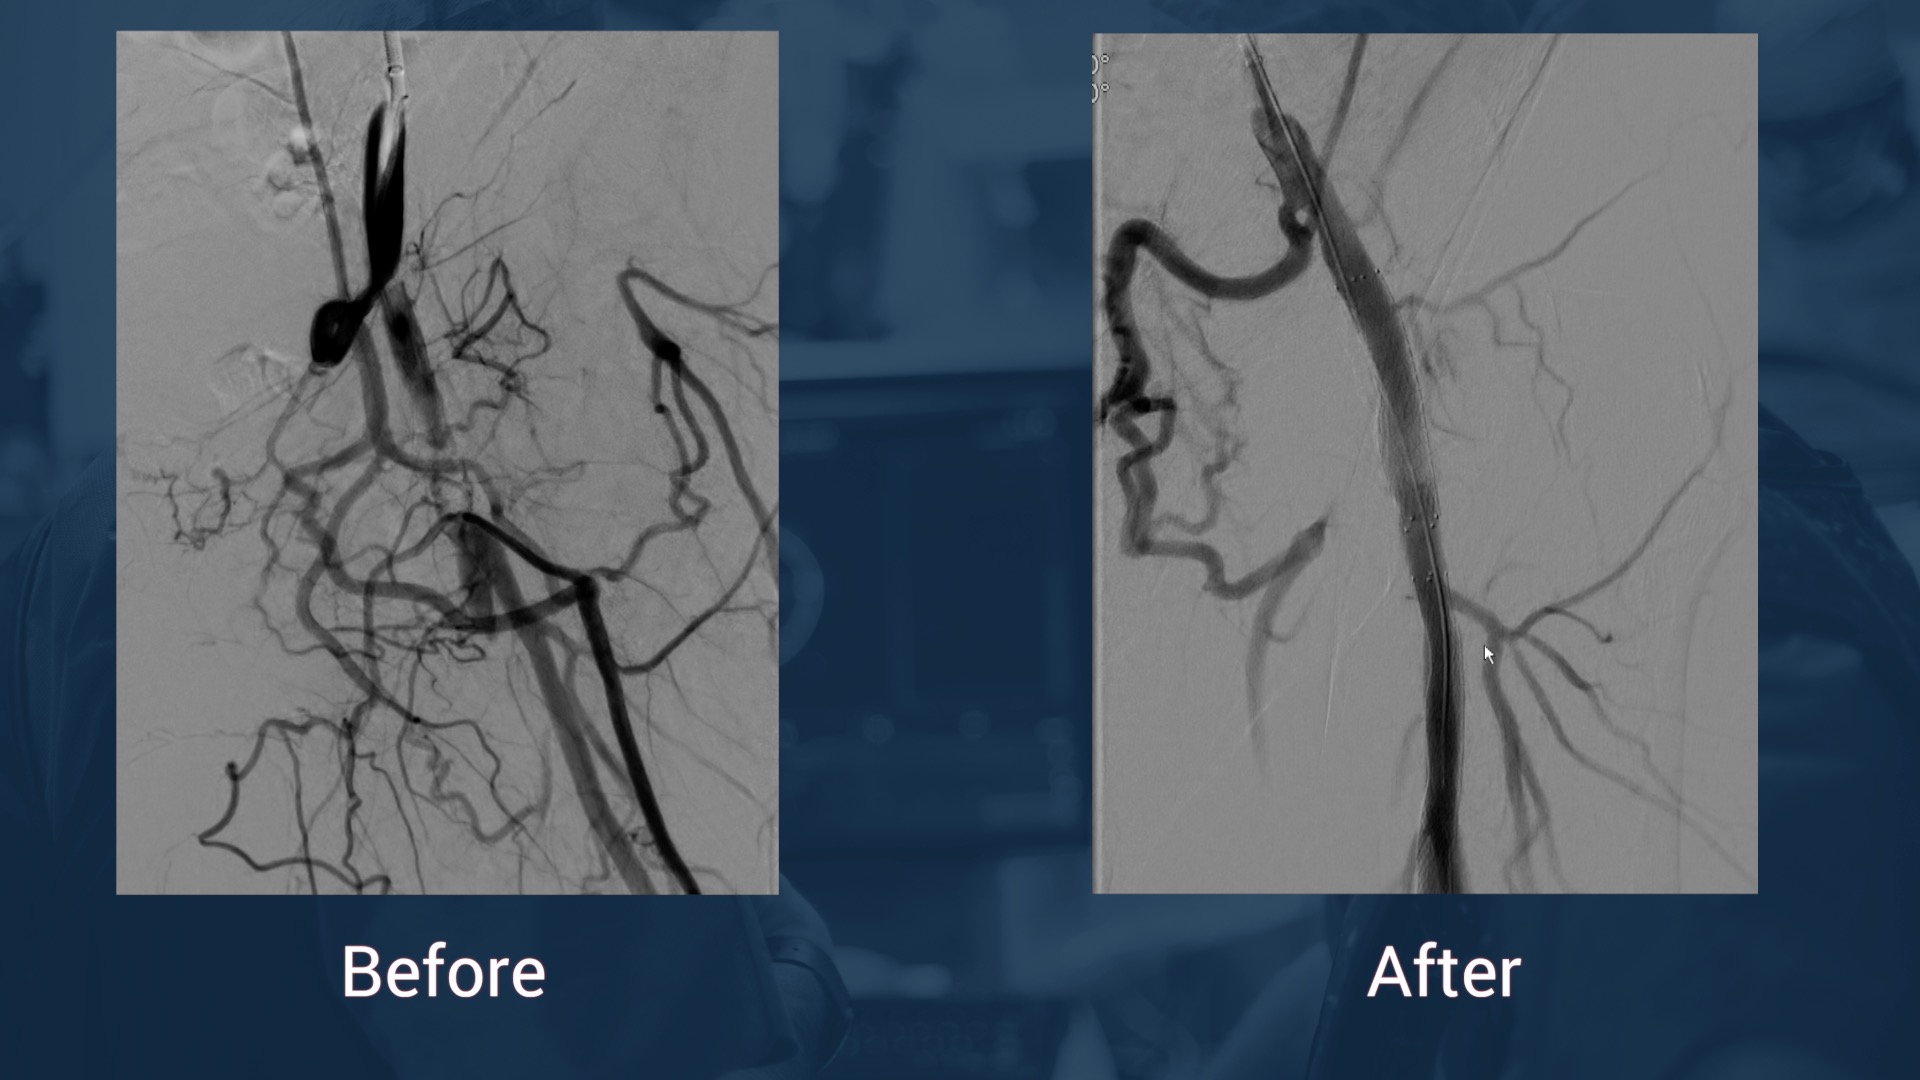

July 23, 2025Flush Occlusion of the Superficial Femoral Artery Managed Using a Retrograde Popliteal Approach: A Case Report Cureus